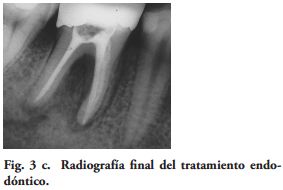

Los exámenes clínicos fueron realizados con un espejo y un explorador agudo. Un control radiográfico fue hecho en cada DPET. La evaluación de las variables relacionada a las restauraciones, fue ciega entre los autores. El Coeficiente Kappa de Cohen (14), en la calidad de las restauraciones y del examen radiográfico, varió de 0.78 a 1 [excelente de acuerdo a la guía de Fleiss (15). En los casos de no concordancia en la calificación, se registró el valor más bajo.

Al momento del examen, 10 (90.9%) EC estaban en función en 10 pacientes. Un molar 26, restaurado con EC, se perdió por enfermedad periodontal después de 12 años y 9 meses en función. Ninguna restauración se desprendió, no hubo recidiva de caries y al examen radiográfico no se observaron lesiones patológicas en los 10 DPET en función (Figs. 1a,1d; 2c; 3c,3d; 4c).